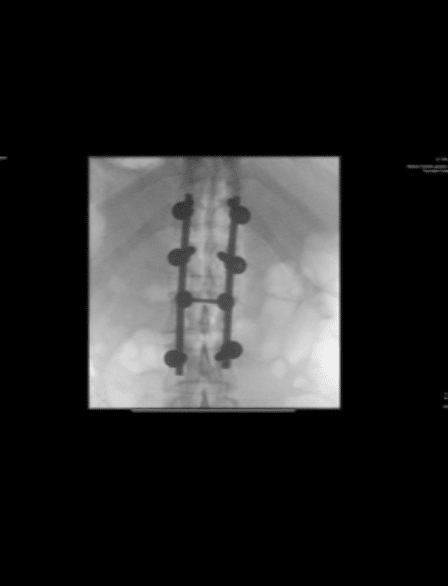

Goerke crashed while jumping through a large triple section and landed extremely short on the jump. The impact of the crash caused the majority of his injuries, fracturing his spine at the L2 vertebrae and broke his left clavicle. He was taken to Klinikum Chemnitz; a local hospital near the Fair where surgeons performed the first of two scheduled surgeries stabilizing his spine with rods. The second surgery to address the left clavicle break is expected to be scheduled this Thursday.